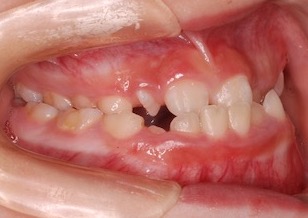

10歳女児の患者さんです。反対咬合(受け口)と叢生(ガタガタの歯並び)を主訴に一般歯科からのご紹介で来院されました。骨格性反対咬合(上下顎骨の前後的な位置不正が原因)の症例でしたが、成長発育期における早期矯正治療を開始できたことにより非抜歯にて反対咬合ならびに叢生の改善ができました。

Before Ⅰ

上顎骨の劣成長に起因する骨格性反対咬合(上下顎骨の前後的な位置不正が原因)で、前歯部は反対咬合となっており咀嚼障害を認めます。 上下顎歯列において叢生(ガタガタの歯並び)と 上下顎歯列の正中線のズレが認められます。 左側上下顎第一大臼歯は交叉咬合となっています。レントゲン所見では、上顎左側犬歯が方向異常にてその隣の側切歯の歯根にぶつかって埋伏していました。